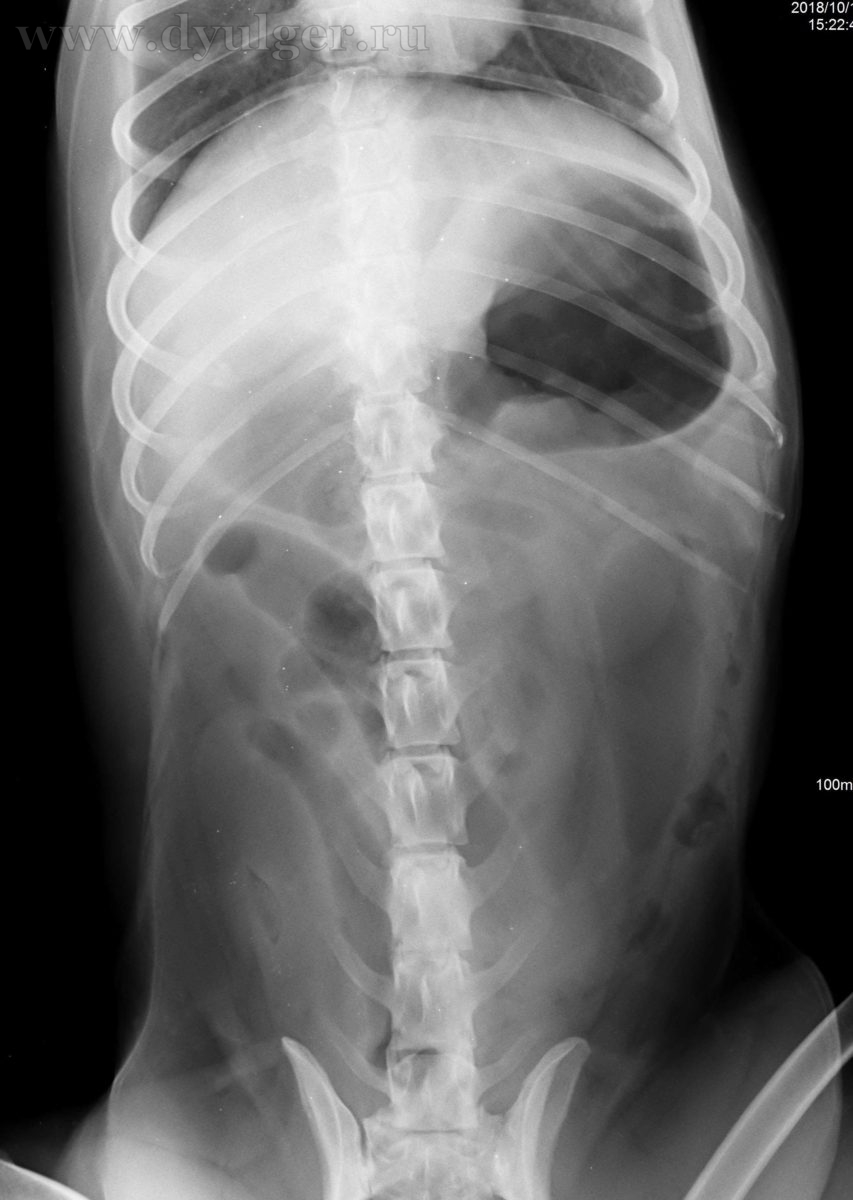

Необычные находки: инородные тела на рентгенограмме брюшной полости